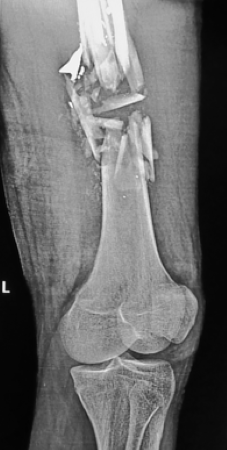

Seventy-nine patients presented with gunshot injuries over the study period, 34(43%) were because of armed robbery attack. The mean age was 35.2 years ±8.8SD with age group 25-44 years being the most commonly affected and male to female ratio of 16:1.The extremities was most injured region in 38.2% and 67.6% of the attacked occurred at night with 20.6% mortality rate. Outcome of the patient and type of weapons used were significantly associated with p =.04.

Armed robbery-related GSI affects predominantly young adults. The extremities were most commonly injured, and weapons of injury, were predominantly low velocity, with a high mortality when fired at close range. There is an increasing need to reduce the prevalence through youth engagement and effective night policing.